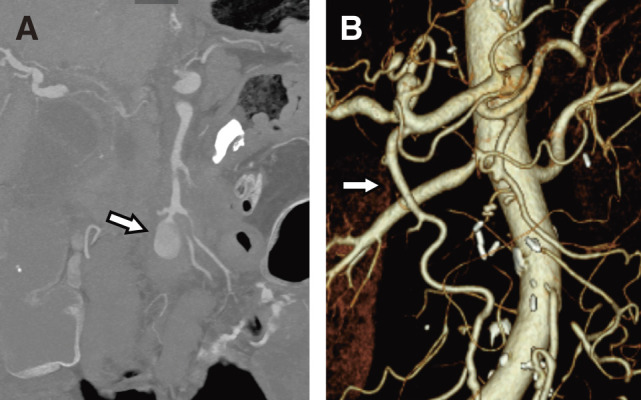

Superior mesenteric artery (SMA) aneurysm and their surgical interventions are rare, leading to infrequent reports of postoperative complications. This report describes 2 cases of refractory diarrhea following vascular reconstruction for infectious SMA aneurysms. Both patients underwent aneurysm resection and SMA reconstruction but experienced persistent diarrhea despite treatment with anti-diarrheal medications. Postoperative diarrhea, a complication observed after resection of the nerve plexus around the SMA in gastrointestinal surgery, may be attributed to intraoperative injury to the nerve plexus in our cases. Though palliative therapy is partially effective, more efficacious management strategies are desirable to address this persistent complication.